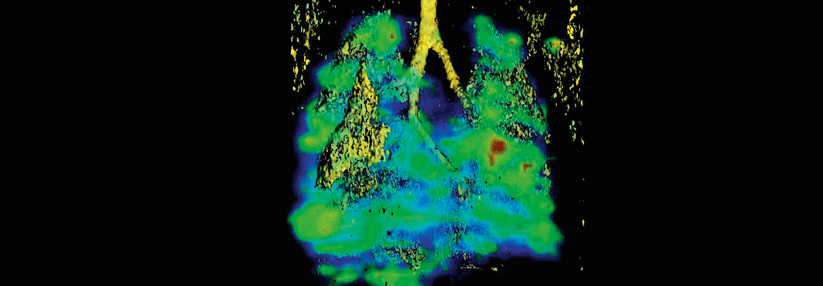

Pruritus: Haut und Psyche leiden unter dem chronischen Juckreiz

© thinkstock Pruritus: Haut und Psyche leiden unter dem chronischen Juckreiz © thinkstock